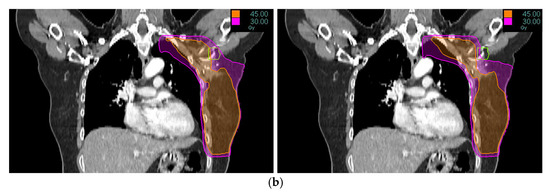

Dosimetric Feasibility of Tomotherapy-Based Selective Axillary Sparing Regional Nodal Irradiation for Lymphedema Risk Reduction in Breast Cancer

by Kwang Hwan Cho, Cheol Wan Lim, Sung-Mo Hur, Zisun Kim, Jae-Hong Jung, Daegun Kim and Seung-Gu Yeo

Medicina 2025, 61(12), 2177; https://doi.org/10.3390/medicina61122177 - 7 Dec 2025

Background and Objectives: The axillary lateral vessel thoracic junction (ALTJ) is a key lymphatic drainage pathway for the arm and a potential structure to spare during regional nodal irradiation (RNI) to reduce lymphedema risk in breast cancer patients. This study aims to [...] Read more.

Background and Objectives: The axillary lateral vessel thoracic junction (ALTJ) is a key lymphatic drainage pathway for the arm and a potential structure to spare during regional nodal irradiation (RNI) to reduce lymphedema risk in breast cancer patients. This study aims to demonstrate the feasibility of ALTJ-sparing radiation therapy (RT) planning using Tomotherapy. Materials and Methods: Ten breast cancer patients who had undergone axillary lymph node dissection and whose dissected axillary levels were excluded from the RNI target volume were included. A TomoDirect intensity-modulated RT plan was generated at a dose of 50 Gy in 25 fractions. The dissected axilla was not designated as an organ at risk (OAR) in the original treatment plan. For this study, the axillary lymph node level I (AXL1) and the ALTJ were delineated retrospectively, with the ALTJ considered an OAR in the newly generated study plan. A total of 20 RT plans (10 per group) were statistically compared using various dose-volume parameters. Results: Compared to the original plans, the study plans with ALTJ as an OAR significantly reduced the incidental dose to both the ALTJ (mean: 41.7 ± 3.4 Gy vs. 27.2 ± 1.3 Gy; p = 0.005) and the AXL1 (mean: 43.9 ± 2.0 Gy vs. 37.7 ± 1.9 Gy; p = 0.005). All other dosimetric parameters (V25Gy, V35Gy, V40Gy, Dmin, Dmax) for the ALTJ were also significantly lower in the study plans. This ALTJ sparing was achieved while maintaining all required dose-volume constraints for target volumes and standard OARs such as the lung and heart. Conclusions: This study demonstrates that simply excluding the dissected axilla from the target volume without designating it as an OAR still results in a substantial incidental dose to this region. Our findings also show the feasibility of using Tomotherapy to selectively spare the axilla, particularly the ALTJ subregion of AXL1, which is critical for lymphedema risk in breast cancer patients. Full article